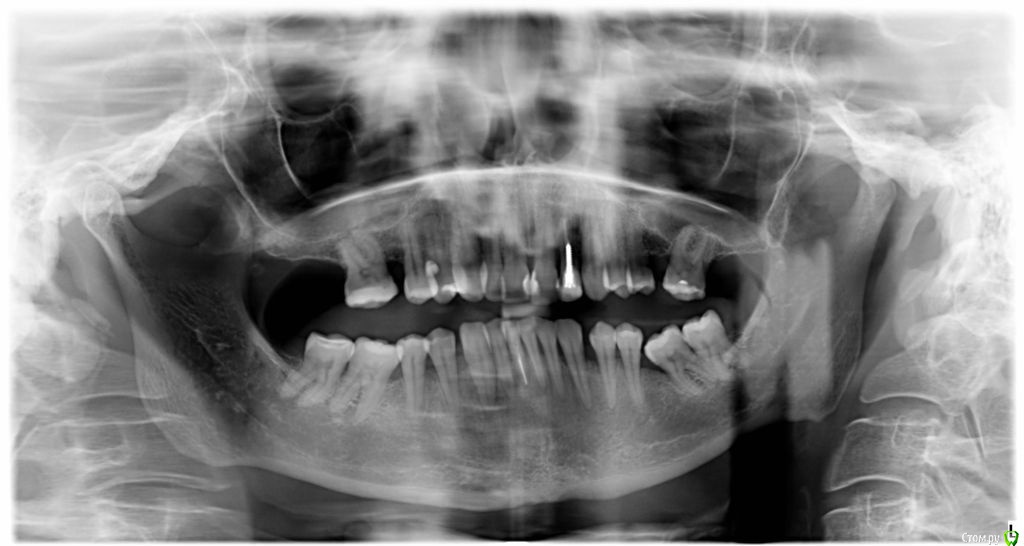

VVQW Опубликовано 6 декабря, 2016 Поделиться Опубликовано 6 декабря, 2016 (изменено) Более 10 лет назад была установлена брекет-система.Лечение было проведено на глаз, анализы и диагностика не проводилась. Спустя время- итог. Сверху перед установкой врач принял решение удалить 6-ки, 8-ки -не выросли. Промежутки между 7-ми и 5-ми - не дотянул и бросил врач. На нижней челюсти системы не было, нижние 6-ки потеряны лет до 14 (в подростковом возрасте). Сейчас процес -усугубляются клиновидки, оголение . Что можно сделать? http://s019.radikal.ru/i641/1612/eb/3498e6cec3f8.jpg http://s018.radikal.ru/i518/1612/73/739600b6d2d1.jpg http://s011.radikal.ru/i318/1612/73/443e1513aaf8.jpg http://s017.radikal.ru/i403/1612/86/73e0dfe4ca62.jpg http://s018.radikal.ru/i518/1612/a2/bd7078537d9e.jpg http://s017.radikal.ru/i417/1612/9d/41b6d1c98666.jpg http://s019.radikal.ru/i642/1612/fe/3222fa19d517.jpg Гипсовых моделей нет, зубы неподвижны. http://s019.radikal.ru/i639/1612/56/1345f17db908.jpg http://s019.radikal.ru/i630/1612/55/145ef7c813b2.jpg http://s017.radikal.ru/i440/1612/c2/74bd4da2643e.jpg http://s008.radikal.ru/i303/1612/b4/e80683ed7d2b.jpg http://s010.radikal.ru/i314/1612/74/6d2f9671b0d5.jpg http://s018.radikal.ru/i502/1612/97/9a15fcf4ddd3.jpg http://s020.radikal.ru/i715/1612/59/9bb4a006621f.jpg Изменено 6 декабря, 2016 пользователем VVQW Ссылка на комментарий